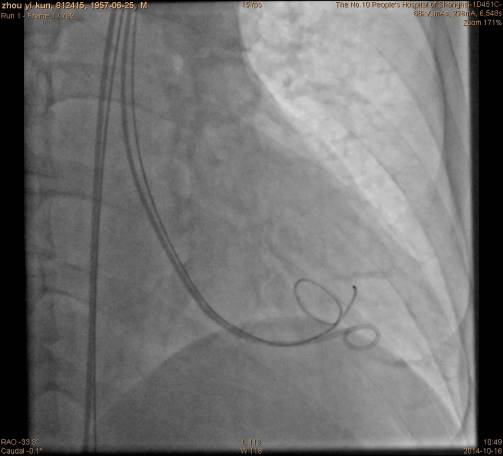

右侧股动脉置入16F鞘管,6FPigtail导管进入左心室,沿猪尾巴置入强生cordis加硬导丝;

沿导丝将16F指引导管置入心尖部;

手术过程指引导管到达左心室: